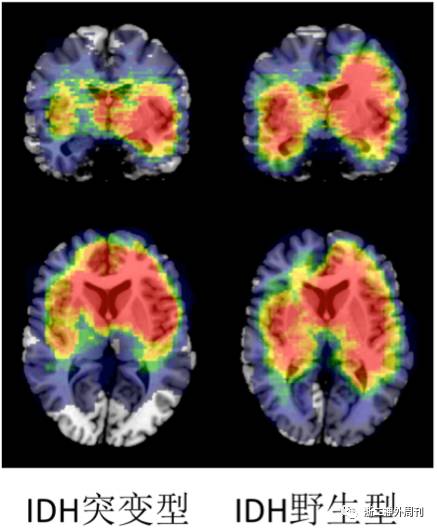

进一步我们分析肿瘤分子特征同肿瘤的位置关系。图4显示IDH基因突变同肿瘤位置的关系。图5显示TERT基因启动子突变同肿瘤位置的关系。图6显示染色体1p19q共缺失状态同肿瘤位置的关系。

图4. 不同IDH基因突变状态的胶质瘤的位置分布特征。